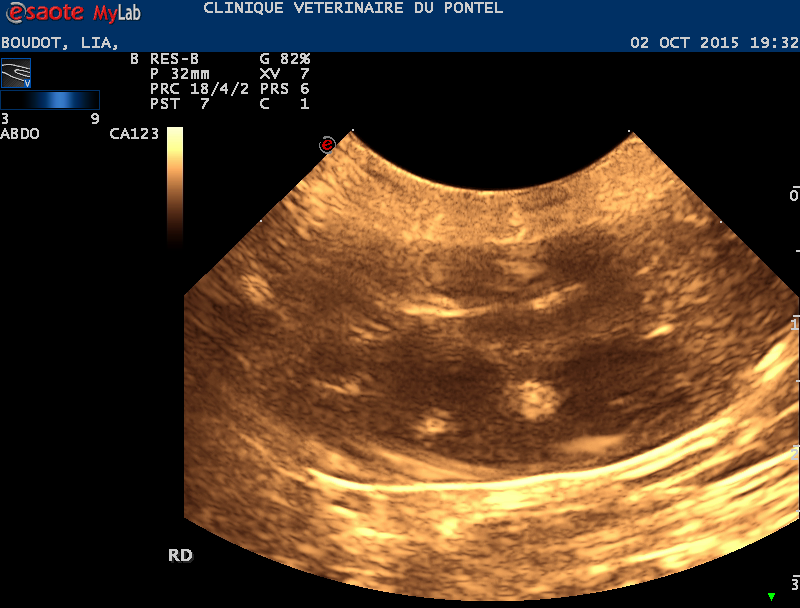

Echographie cardiaque/ abdominale

L'échographie cardiaque permet d' affiner l'origine des troubles cardiaques et de prescrire en urgence le meilleur traitement.